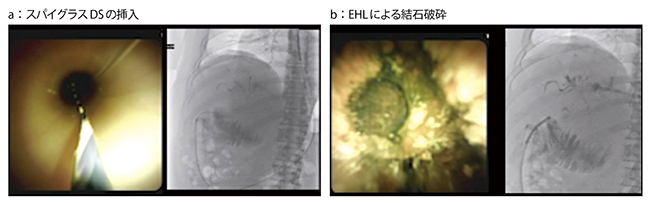

症例2は、三管合流部に胆管結石が嵌頓してMirizzi症候群となり、黄疸を来した症例である。本症例は、機械的砕石具での破砕は困難と考えられたため、始めからスパイグラスデジタル内視鏡胆管・膵管鏡システム(スパイグラスDS:ボストン・サイエンティフィック社製)を使用した。かなり硬いコレステロール結石であったが、2回目のEHLにて十分に破砕でき、バスケットカテーテルにて結石を除去することができた(図2)。

図2 症例2:三管合流部の胆管結石嵌頓症例へのEHL